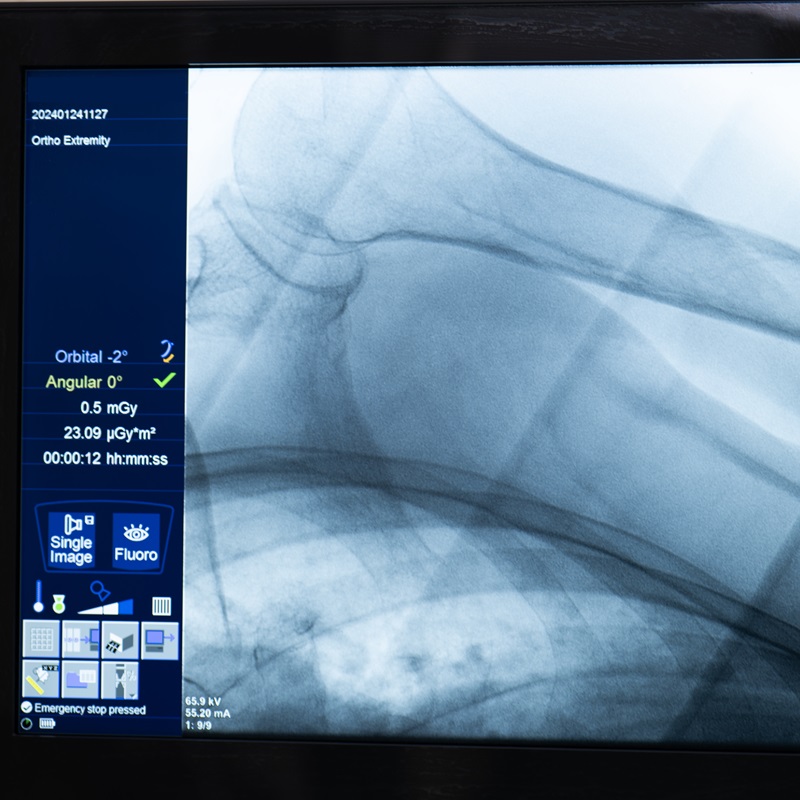

- цифрова рентгенографія;

- апарат Canon для цифрової рентгенографії;

Для визначення детальної клінічної картини ушкодження та не припустити закритого перелому після огляду лікарем проводиться цифрова рентгенографія. Рентген виконується на апараті Canon. У разі необхідності призначається КТ.